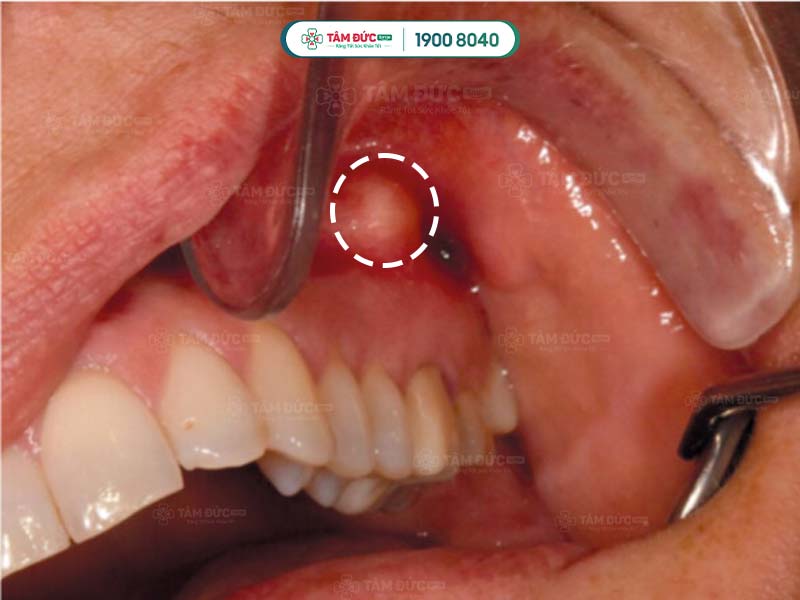

Nhiễm trùng chân răng hàm trên

- Áp xe răng: Đây là bệnh nhiễm trùng nghiêm trọng ở chân răng, có thể gây sưng, đỏ, đau nhức dữ dội, sốt, thậm chí là sưng mặt.

Nhiễm trùng nướu răng cửa